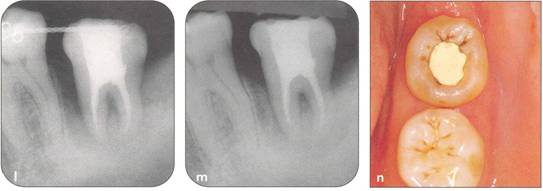

Fi 545e45f g 5-4f Extracted second molar, which will be discarded. Fi 545e45f g Extracted donor tooth. The amount of periodontalligament is adequate. Transplantation was performed 6 weeks after extraction of the tooth from the recipient site. Fi 545e45f g 5-4h View of the donor site and preparation of the recipient site. |

Fi 545e45f g 5-4i After the gingival flap has been sutured and the donor tooth has been splinted. The distal aspect of the donor tooth is closed as tightly as possible. Fi 545e45f g 5-4j After transplantation. Fi 545e45f g 5-4k Two weeks after trans plantation |

Fi 545e45f g 5-41 Six weeks after transplantation. The root canals have been cleaned, shaped, and filled with calcium hydroxide. Fi 545e45f g 5-4m Three months after transplantation. The radiograph was taken after removing the splint. Fi 545e45f g 5-4n Seven months after transplantation. |